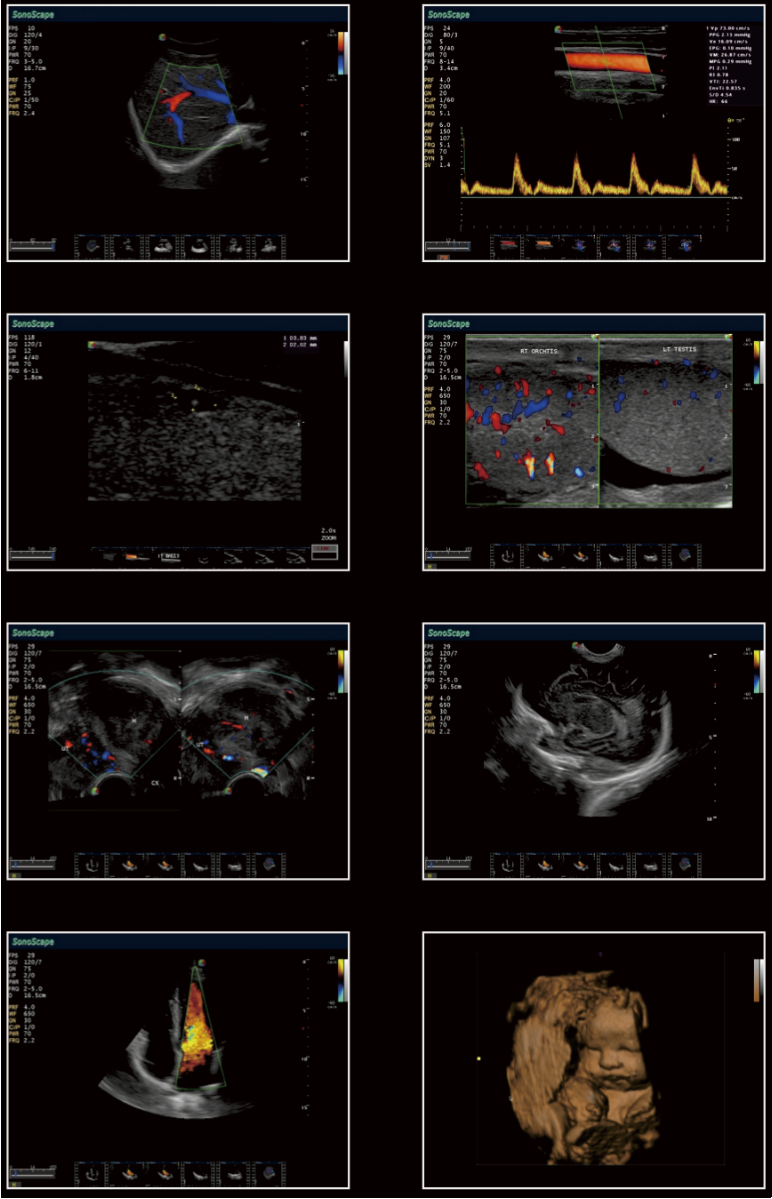

Detecta los detalles más temprano en el primer trimestre en los exámenes de ginecología, mejora su confianza en el diagnóstico. A excepción de la calidad de 3D/4D, S9 también permite excelente imagen 2D bajo diagnóstico 3D/4D endovaginal, lo que aumenta la capacidad de diagnóstico y de la satisfacción de las pacientes obstétricas.

S9 puede proporcionar una alta densidad de la sonda phased array para satisfacer las necesidades tanto de alta velocidad de fotogramas y la resolución de image premiun en la obtención de imágenes cardíacas. Gracias por la alta sensibilidad de mapeo Doppler color del SonoScape, S9 muestra el diagnóstico cardiaco precisa más allá de su imaginación.